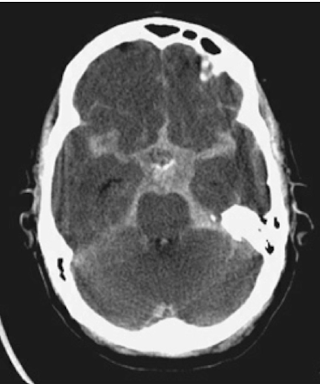

Q

Where is the blood

A

intraventricular

11

subarachnoid (cisterns/circle of willis)